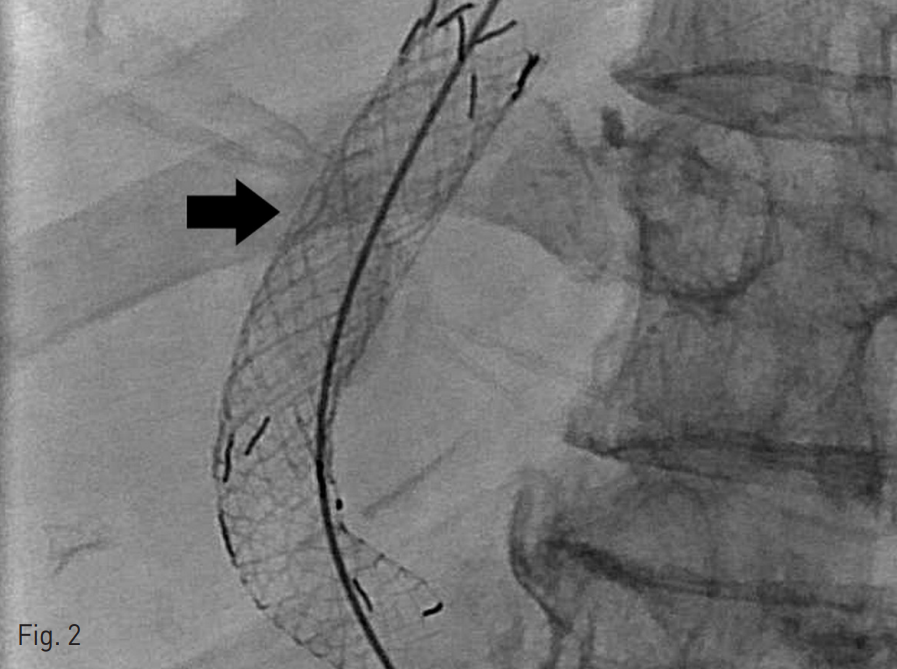

Fig. 2

After first revision, one-point tied (arrow) constrained stent is positioned at TIPS tract

초음파 유도 하에 오른목정맥을 천자하여 8 Fr sheath를 삽입하였다. 기존 TIPS tract를 selection한 후 문맥과 간정맥에서 압력을 잰 결과, 압력차이는 7 mmHg였다. 10mm x 6cm stent graft (S&G Biotech, Sung-nam, Korea)의 가운데를 묶어 장구 형태로 최소 직경을 6 mm로 만들어서 (Fig. 1) 유도철사를 따라 이전에 삽입하였던 10mm stent 내부에 설치하였다 (Fig. 2). 시술 이후 문맥-간정맥 압력 차는 8 mmHg로 측정되었다.